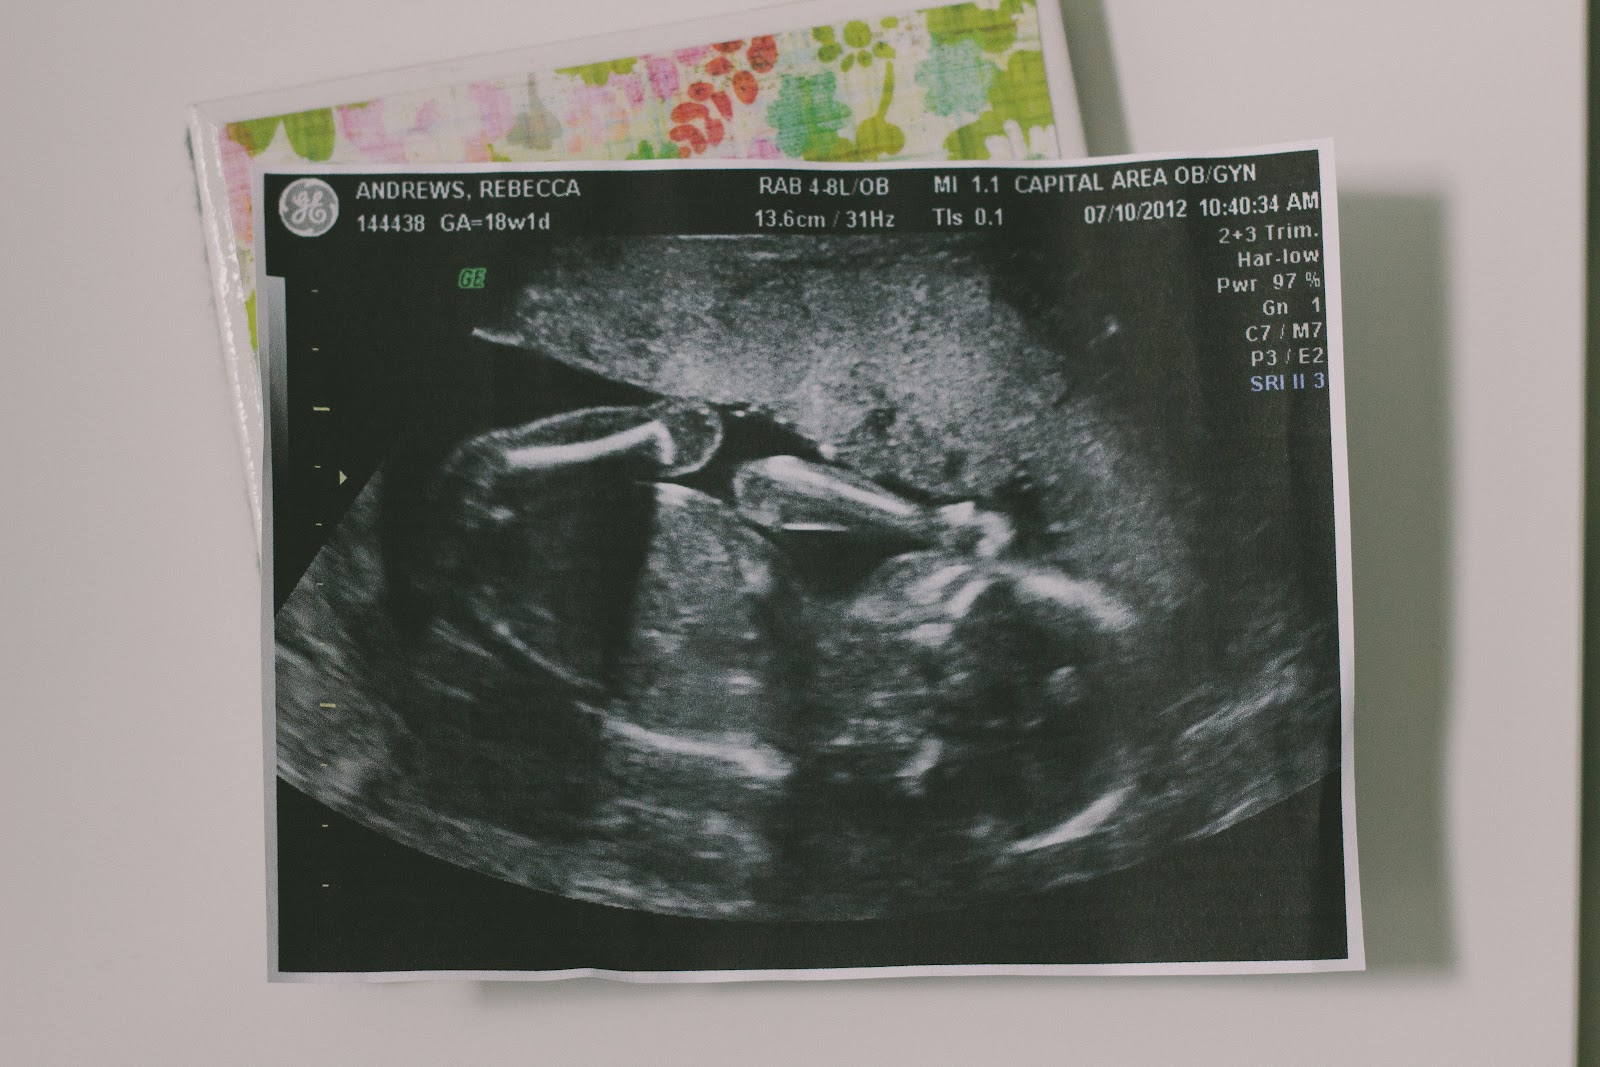

and then i spent some time examining the second picture. 20 weeks and you can see his entire frame - the spine, brain, feet, hands - everything! astounding, isn't it?